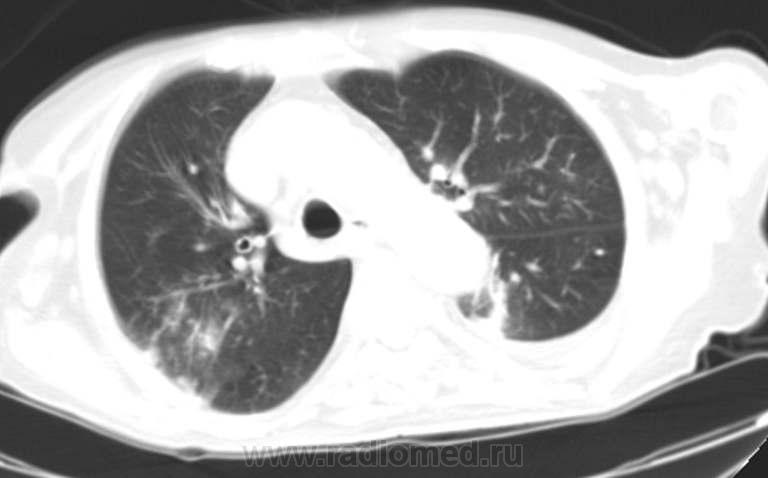

Прошу коллег высказать мнение о возможном генезе полостей в легких (туберкулезные? другие?). Б-я, 80 лет. Состояние тяжелое. Доставлена по 03. КТ,  рентгенограмма ОГК представлены. Жду Вашей помощи. С уважением Nik

посчитал количество синдромов:множественные кольцевидные тени(там несколько вариантов течения -в инфильтрате -распад,с толстыми стенками-сформировавшийся или реактивация , с тонкими стенками-старые ),уплотнение по типу инфильтрации с распадом  ,перибронховаскулярное уплотнение ,симптом "дерева в почках",ацино-нодулярные очаги (можественные ) местами слившиеся ,кальцинированные очаги ,интерстициальные изменения,в S10 справа субплеврально участок уплотнения по типу консолидации ,широким основанием прилежащий к плевре со сближением сосудов (исключить инфаркт).мое мнение -явный туберкулез без сомнений !!но необходимо контрастное исследование для исключения тэла -возможно сегментерной ветви S10

Консолидация с воздушной бронхограммой в S4-5 слева не связана с полостями там же (мне полости кажутся тонкостенными - кисты?); думаю, что эти процессы параллельны. На цирроз не похоже, не видно объемного уменьшения. Если острая клиника, то больше шансов, что консолидация острая. Т.е. либо пневмония, либо инфаркт, либо инфарктная пневмония. Плюсом выпот.

Справа в S6 две полости, одна с уровнем жидкости, вторая с неравномерной толщиной стенки. Вроде как очаги есть. Но сканы с дыхательными артефактами, о какой-то тонкой интерпретации лично мне говорить сложно.

установлен на секции. Туберкулеза нет. Справа деструктивная пневмония. Слева инфарктная пневмония с распадом. К  врачам сайта. Какие признаки позволили Вам столь уверенно и правильно поставить диагноз ТЭЛА справа.  Жду ответ. С уважением, Nik

Пневмонии на КТ выглядят либо как участки помутнения по типу матового стекла, либо как консолидация, т.е. уплотнение. Характерен симптом воздушной бронхограммы, т.е. видны просветы бронхов на фоне уплотнения, как в приведенном случае слева в язычковых сегментах.

Без контрастирования сосудов и визуализации тромба в просвете ЛА и её веток, можно лишь предполагать инфаркт по треугольной форме консолидации, широким основанием к плевре, верхушкой к корню, без уменьшения объема пораженной анатомической области. Косвенные признаки ТЭЛА: увеличение диаметра сосуда, к которому направлена верхушка треугольника; выпот; зона просветления (central lucencies) в толще инфракта превосходящая диаметром бронхи (правда, в данном случае в "язычках" больно четкие и ровные контуры для этого симптома). Клиника +/-, поскольку не все инфаркты сопровождаются клиникой.

То, что справа, может тоже быть последствием инфаркта и некроза.